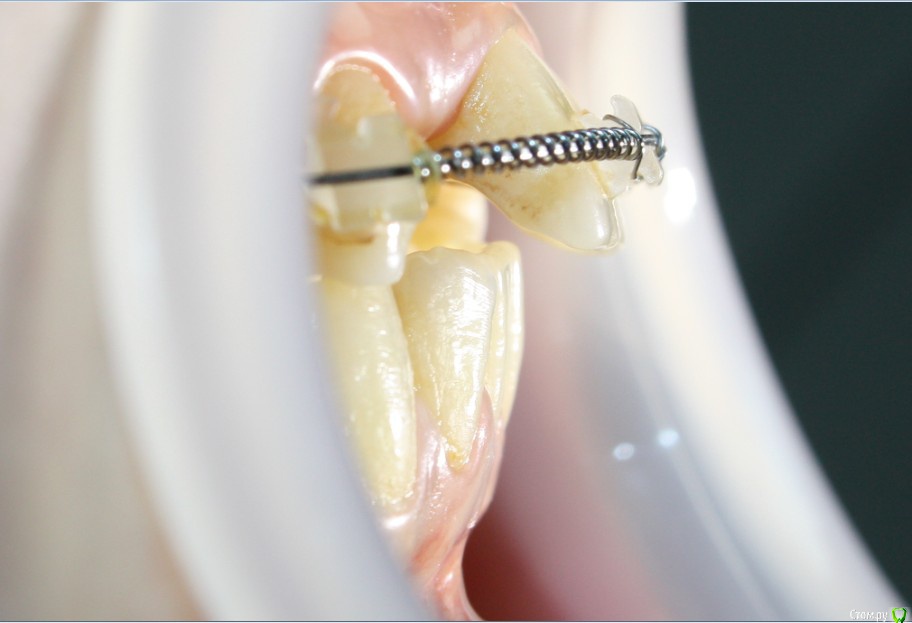

Фото сегодня:post-461-0-94195200-1456407270_thumb.jpgpost-461-0-97652100-1456407271_thumb.jpgpost-461-0-40898500-1456407273_thumb.jpgpost-461-0-68973300-1456407274_thumb.jpgpost-461-0-88108800-1456407275_thumb.jpgpost-461-0-99061300-1456407276_thumb.jpgpost-461-0-92547500-1456407277_thumb.jpgpost-461-0-02811200-1456407279_thumb.jpgpost-461-0-05035300-1456407280_thumb.jpgpost-461-0-27197600-1456407281_thumb.jpg